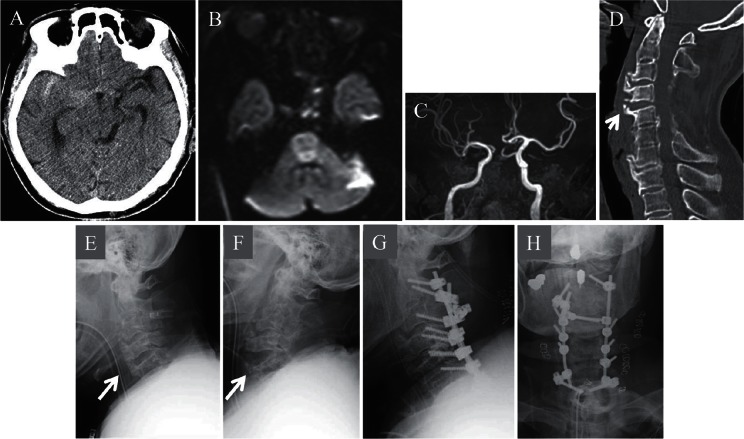

Fig. 1.

A case of cervical spinal fracture with diffuse idiopathic skeletal hyperostosis (DISH) accompanying traumatic subarachnoid hemorrhage. After falling from a low height, a 79-year-old man presented with a laceration of the forehead. His consciousness level was 300 (JCS). He was admitted to the Department of Neurosurgery because head CT and MRI scans revealed traumatic subarachnoid hemorrhage (A). MRI and MR angiography detected pontine infarction and decreased blood flow in the vertebrobasilar artery (B, C). Cervical CT detected a small crack (arrow) in the anterior osteophyte of C4/5 in the setting of ankylosed spine due to DISH (D). Dynamic cervical spine XP showed an extension fracture through the C4/5 disc space (E, F). After 30 days of conservative treatment to stabilize his vital signs, he underwent posterior fixation surgery (G, H).